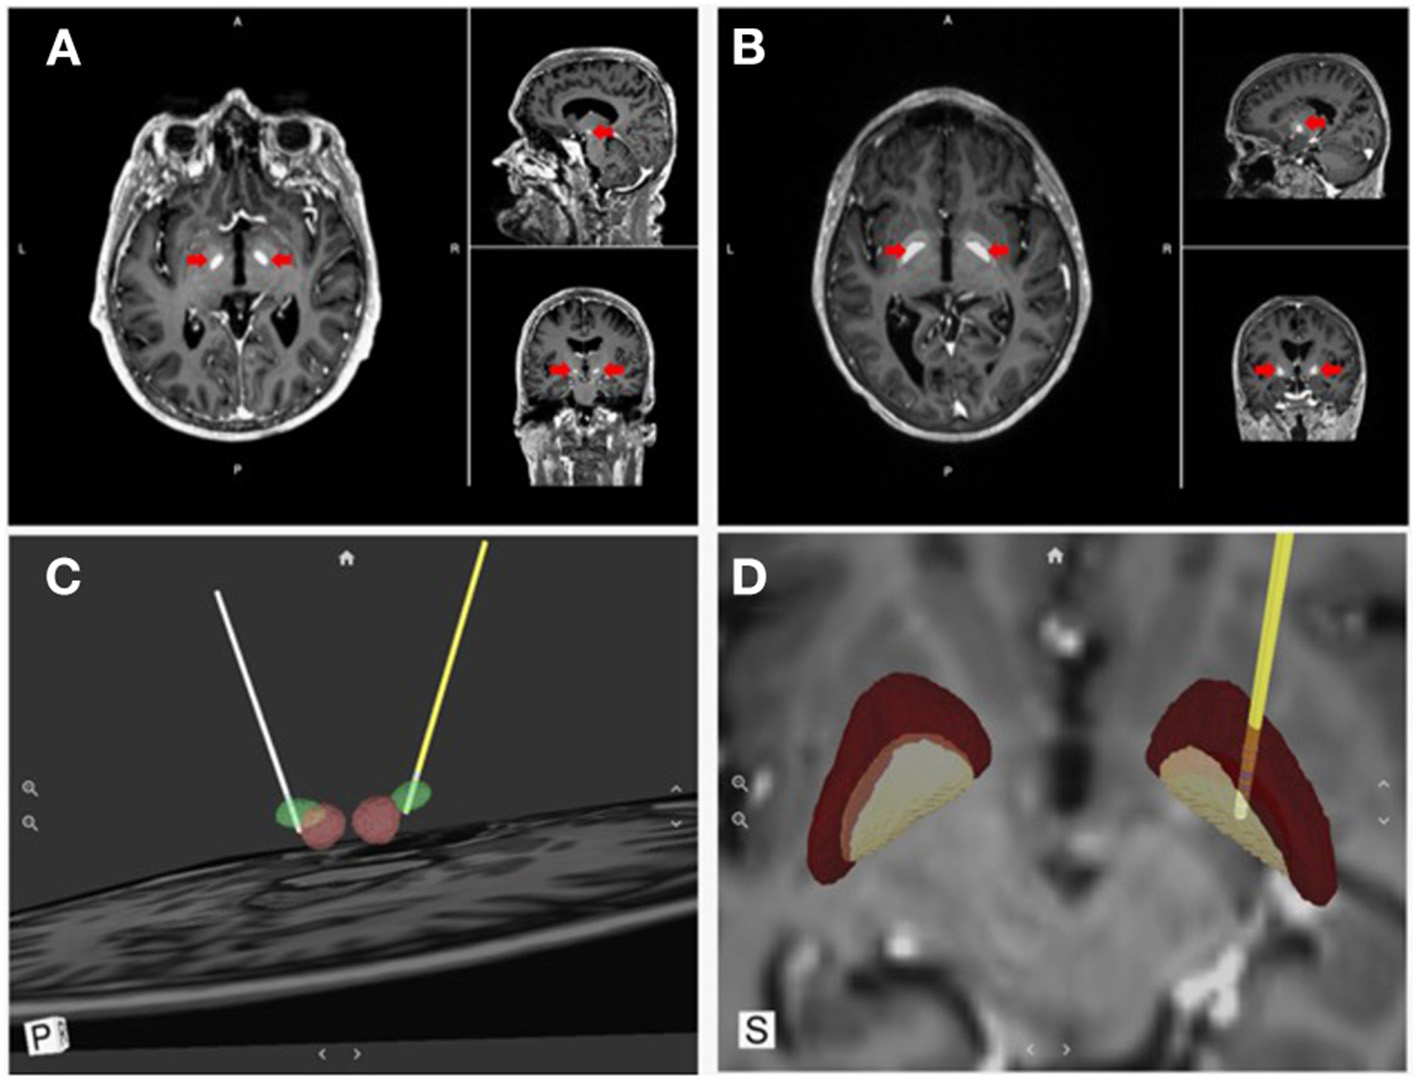

Figure 4

Direct visualization of DBS targets and lead location. Surgical Information Sciences (SIS), provides a patient-specific model of DBS targets using the patient's own enhanced clinical MR image. (A,B) shows alpha maps visualizing the STN and GPi, respectively (red arrows); (C,D) show 3D reconstructions of the intended targets registered with the DBS lead location in respect to the anatomical structures (STN & GPi, respectively).

Visualization tools have also been developed to support an “image-guided” programming approach based on reconstructing the patient-specific anatomy from magnetic resonance imaging (MRI) and computerized tomography (CT) data. One such visualization tool, developed by Surgical Information Sciences (SIS), provides a patient-specific, 3D anatomical model of specific brain structures using the patient's own enhanced clinical MR image (Figure 4). The technology makes use of the fact that some structures in the brain, specifically the STN and the lamina/border between the GPI and internal capsule (IC), are not easily visualized in 1.5T or 3T standard clinical MRI but are better visualized using high-resolution and high-contrast 7T (7 Tesla) MRI (78). The SIS approach uses pre-trained deep learning neural network models, based on these ultra-high-resolution 7T MRIs, to be applied to a patient's clinical image to predict the shape and position of the patient's specific brain structures of interest (i.e., STN or GPi/GPe) (79, 80). The output of the SIS System can then be used for planning stereotactic surgical procedures. The company has validated the accuracy of the STN and GPi predicted locations within 1 mm of the ground truth locations (81). The system can locate and identify implanted leads visible in post-operative CT images and present them in a 3D model in relation to the predicted brain structure from the preoperative processing. These unique features can provide feedback to the surgeon regarding the final location of the lead compared to the surgical plan, as well as inform the programming neurologist about the lead location and contact orientation in relation to anatomical and physiological targets to reduce programming complexity. Visualization tools also allow modeling the VTA generated by various stimulation settings to identify the ones with the highest probability of success (maximal benefits and minimal side effects). Examples include Medtronic SureTune™ and Boston Scientific GUIDE™ XT, which use a patient-specific atlas to provide visualization. Potential shortcomings are represented by the inability to account for individual electrode impedances, axons orientation, and brain tissue inhomogeneity. These tools' accuracy is also limited by axial rotation or vertical migration of the DBS lead that may occur after the image has been acquired.